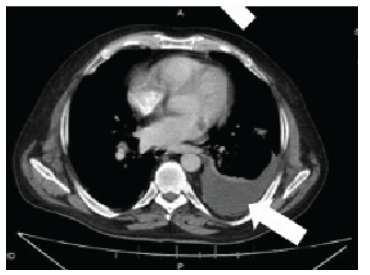

Case report: This case discusses a patient with intermittent abdominal pain and weight loss, which led to the diagnosis and treatment of a GSF and DLBCL. The patient later went into remission for his DLBCL but succumbed to respiratory failure from a secondary abdominal-pleural fistula formation. Gastrosplenic fistulas have the potential to cause fatal, massive, upper gastrointestinal hemorrhages, infections, other fistulas, or esophageal obstructions. A delay in diagnosis corresponds with a higher morbidity and mortality; thus, prompt detection and treatment are imperative. The management of GSFs is complex and requires a multidisciplinary approach to care.